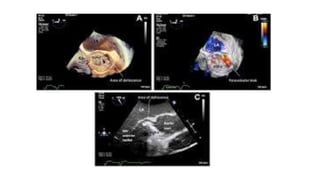

PROSTHETIC VALVE ENDOCARDITIS

• Prosthetic valve dehiscence is highly suggestive of IE.

• Dehiscence can be the only manifestation of IE with a prosthetic

valve in the absence of vegetation or abscess

• A valve rocking motion may indicate valve dehiscence.

• Paravalvular regurgitation may also indicate prosthetic valve

endocarditis but should be compared with any prior paravalvular

regurgitation

• TEE solves this problem for mitral prostheses and improves it for

aortic prostheses .However, when both mitral and aortic prostheses

are present, the mitral device tends to obscure the aortic valve.

Tricuspid and pulmonic devices pose similar problems.

• 30.

PROSTHETIC VALVE ENDOCARDITIS •Prosthetic valve dehiscence is highly suggestive of IE. • Dehiscence can be the only manifestation of IE with a prosthetic valve in the absence of vegetation or abscess • A valve rocking motion may indicate valve dehiscence. • Paravalvular regurgitation may also indicate prosthetic valve endocarditis but should be compared with any prior paravalvular regurgitation • TEE solves this problem for mitral prostheses and improves it for aortic prostheses .However, when both mitral and aortic prostheses are present, the mitral device tends to obscure the aortic valve. Tricuspid and pulmonic devices pose similar problems.